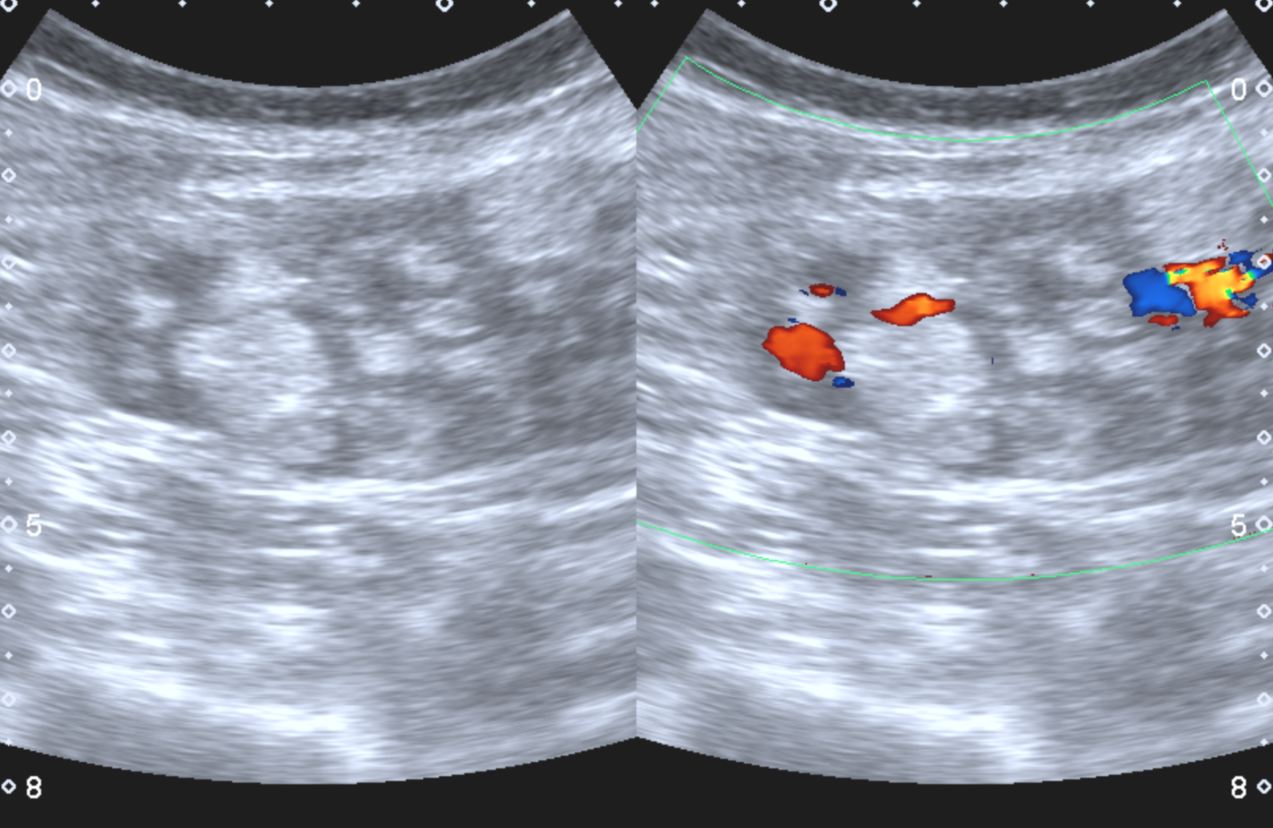

A 45 year old female patient was referred by her GP for a renal ultrasound to investigate hypertension resistant to drug treatment. She was otherwise in good health and had no previous medical history of note or relevant family history. Representative ultrasound images of the kidneys are shown in Figures 1 and 2.